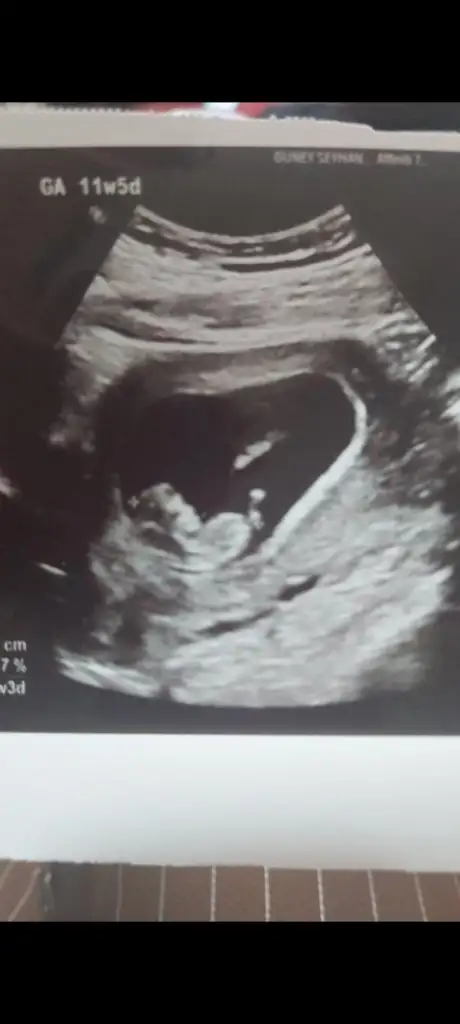

aysesm Yeni Üye Anneler Kulübü Kayıtlı Üye 12 Ocak 2025 64 22 3 24 24 Şubat 2025 Konu Sahibi Konu Sahibi fistik su #10 dahabellidegil .!.: Sizin de konu sahibininki de kız bence.. tabii hayırlısı olsun Genişletmek için tıkla... Benim bebeğimin cinsiyeti ne sizce 7+5 karından Eklentiler IMG_8343.webp 31,9 KB · Görüntüleme: 72

dahabellidegil .!.: Sizin de konu sahibininki de kız bence.. tabii hayırlısı olsun Genişletmek için tıkla... Benim bebeğimin cinsiyeti ne sizce 7+5 karından

dahabellidegil 💜♍️❤️ 💙♒️ 💗♈️ Anneler Kulübü Kayıtlı Üye 11 Mayıs 2022 2.896 En iyi cevaplar 1 3.429 83 26 Şubat 2025 Konu Sahibi Konu Sahibi fistik su #11 Erkek gibi hayırlısı olsun tabii